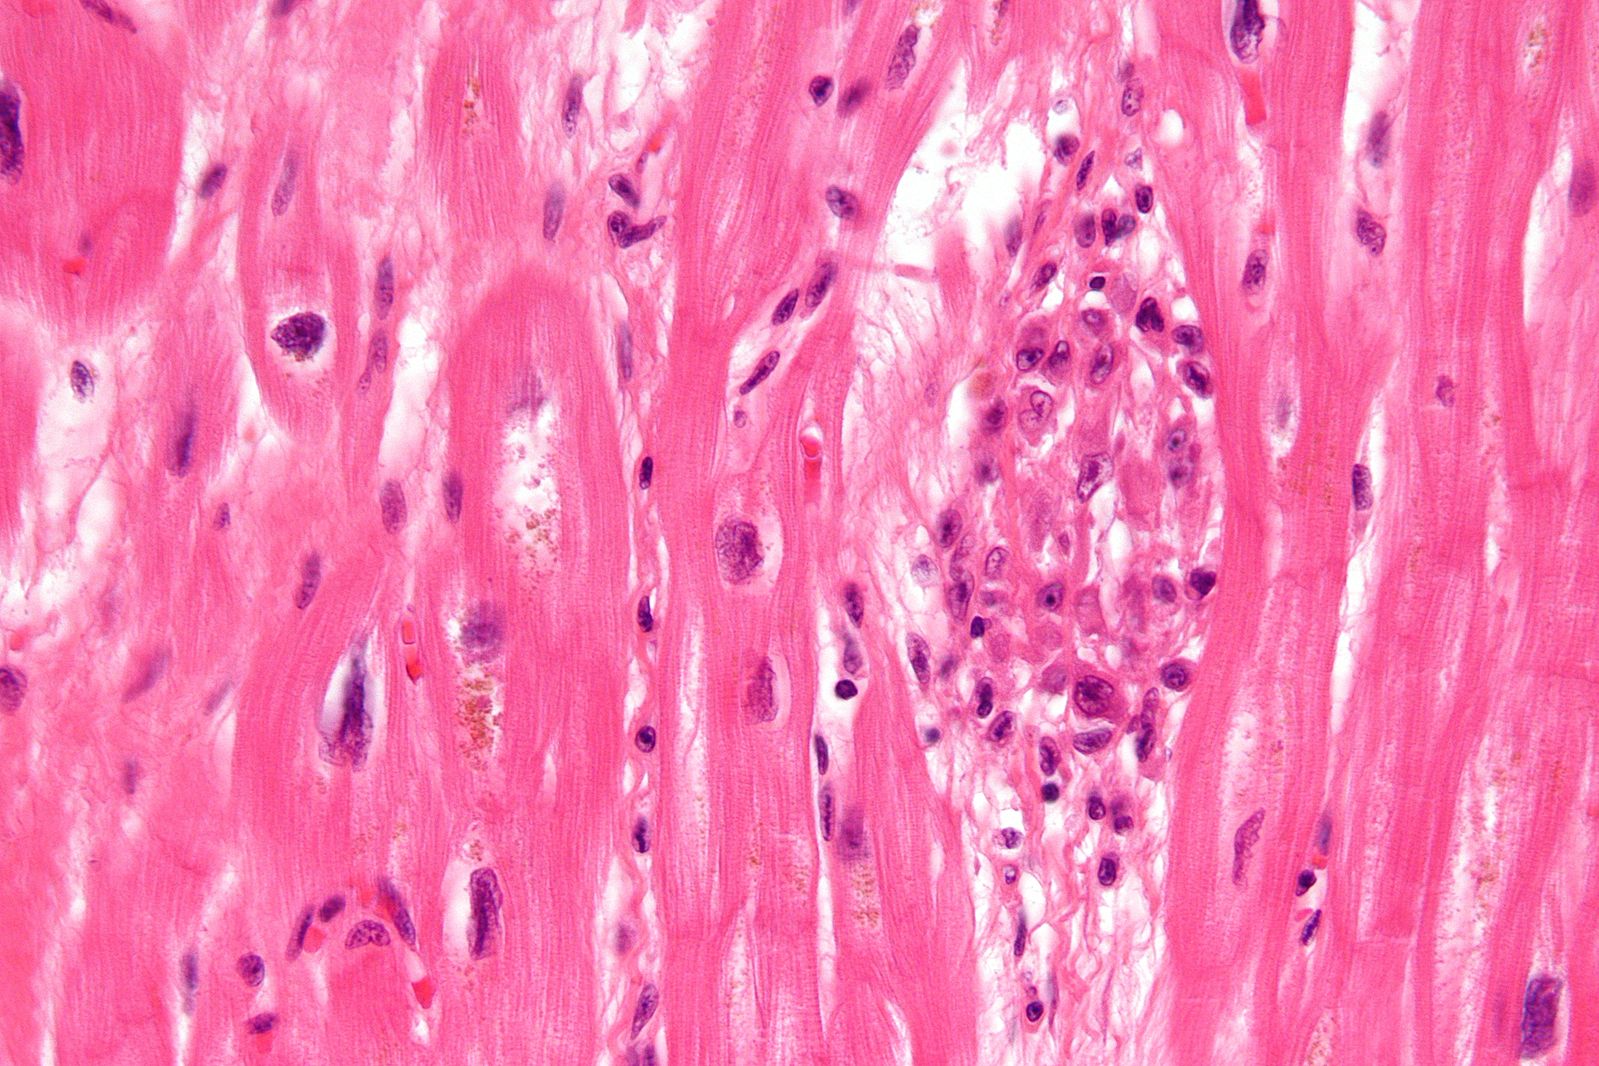

- Myocarditis – localized lesions called Aschoffbodies, may interfere with conduction

-

Micrograph of rheumatic heart disease.